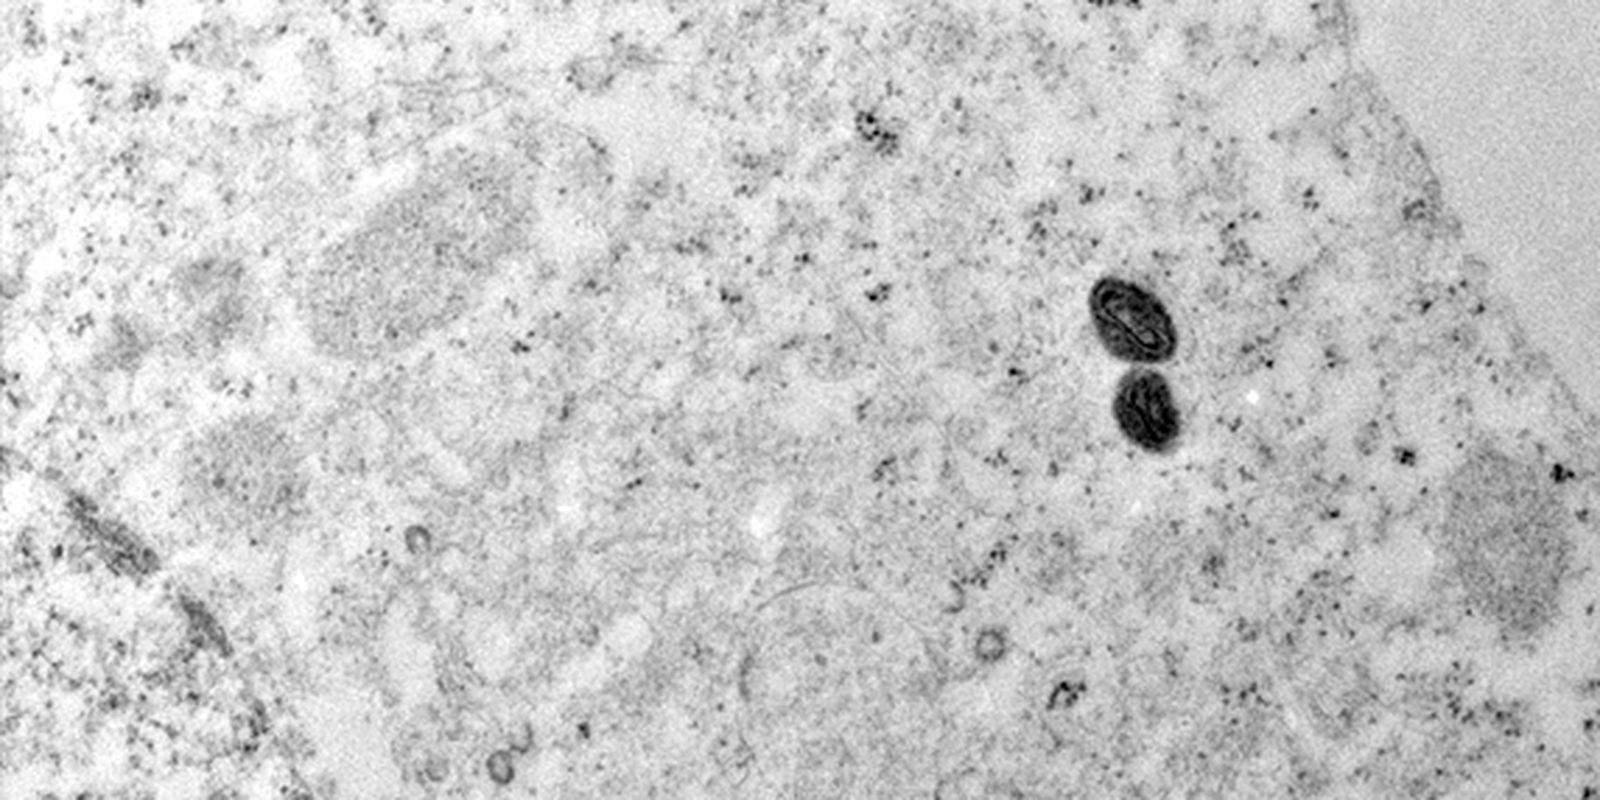

No comunicado, o governo brasileiro reforçou que a variante 1b da mpox, que levou a Organização Mundial da Saúde (OMS) a declarar emergência em saúde pública de importância internacional, não está em circulação no Brasil. Em 2024, o país confirmou 791 casos da doença, mas todos da variante 2b, já conhecida.